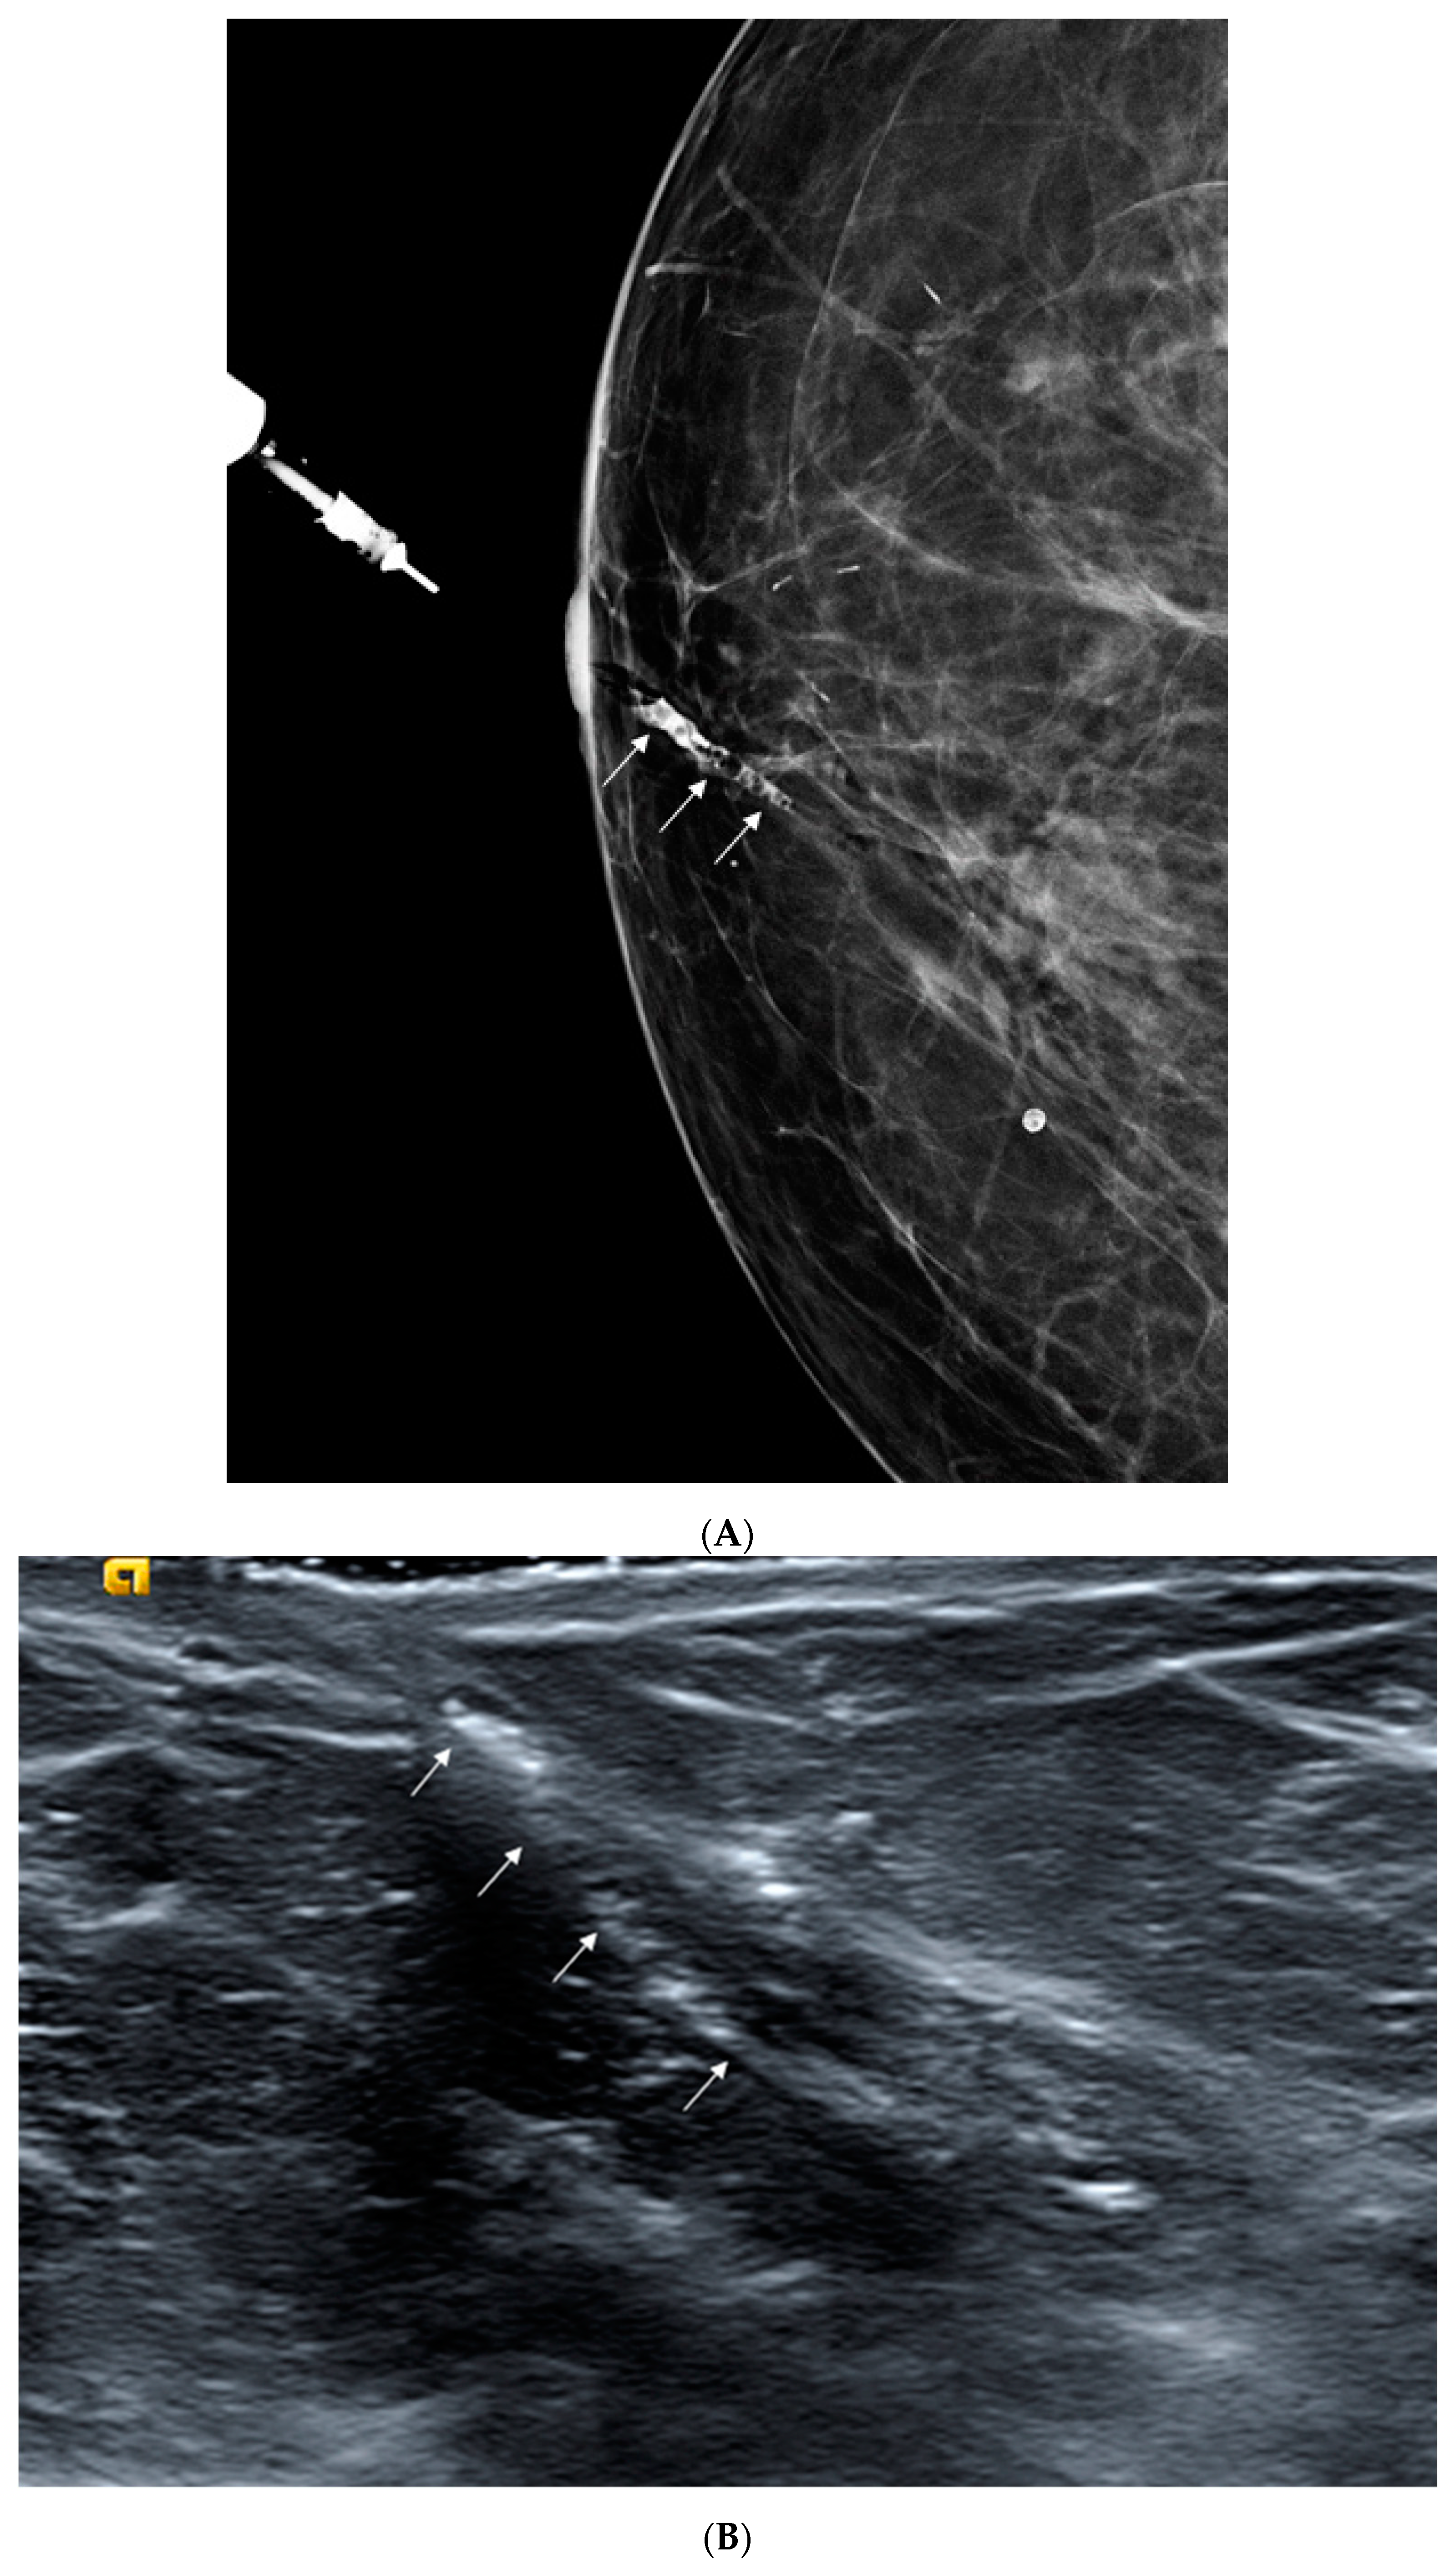

2.2. Galactography

2.3. Sonogalactography